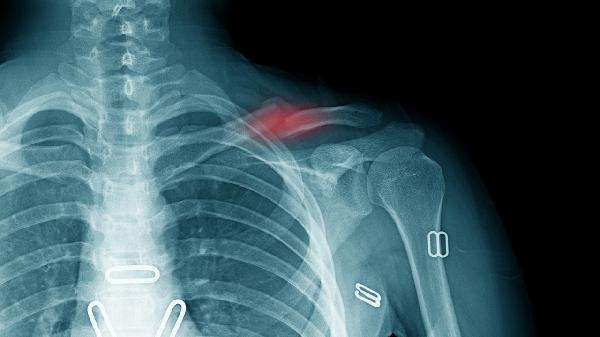

骨折延迟愈合通常发生在骨折后3-6个月内,表现为骨痂形成缓慢或骨折线模糊但未消失,可能因局部血供不足、固定不稳定或感染等因素导致。此时通过调整固定方式、改善营养或物理治疗仍可能促进愈合。骨折不愈合则指骨折超过9个月仍无愈合迹象,X线显示骨折端硬化、髓腔封闭或假关节形成,常需手术干预如植骨或内固定。

延迟愈合的骨折端仍存在纤维软骨组织或少量骨痂,局部可能存在轻度炎症反应但无完全生物学活性丧失。不愈合时骨折端被致密纤维组织填充,形成滑膜假关节或萎缩性骨端,成骨细胞活性完全停止,常伴随骨质疏松或骨吸收现象。